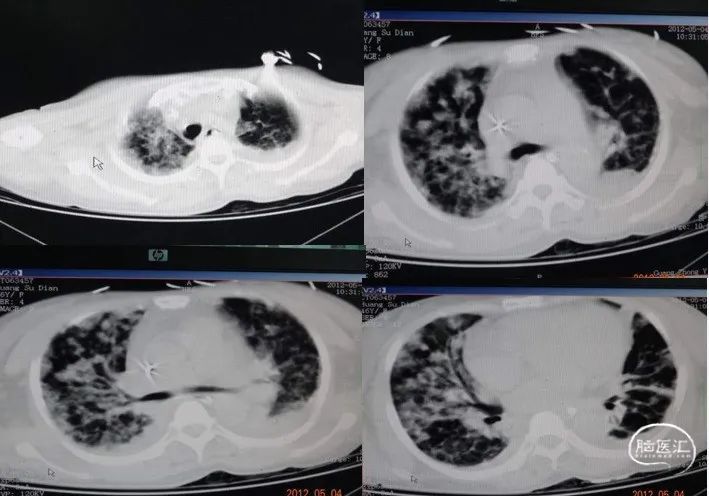

重症脑损伤与急性呼吸窘迫综合征(ARDS):一般临床经验认为,重型脑损伤患者处于意识障碍或昏迷状态,肺部听诊可闻及痰鸣音、湿啰音等呼吸道梗阻或通气不良表现,呼吸频率加快(≥30次/min),PaO2<90 mmHg并呈持续下降趋势,应考虑病人有发展为ARDS的趋势,及早处理对病人的治疗效果非常明显。

重症脑损伤与神经源性肺水肿(NPE):

机制:因肺小静脉、肾上腺素敏感性增加,儿茶酚胺风暴导致大量血容量从体循环到肺循环,另外,因延髓和下丘脑得损伤也会引起神经性源性肺水肿。临床表现起病急,早期出现呼吸困难,伴有大量血性泡沫痰,两肺湿罗音及血压升高。病程进展迅速,治疗困难,病死率高。